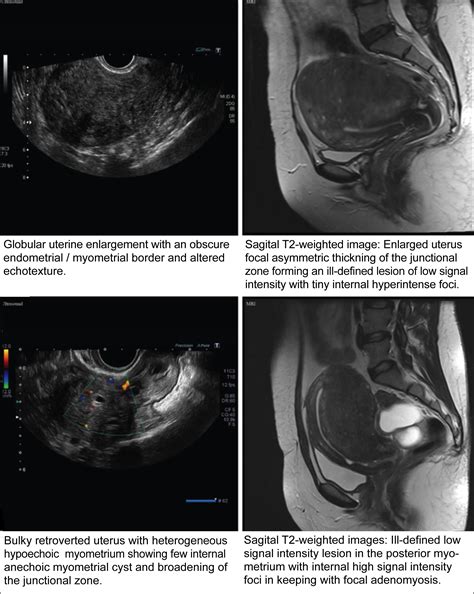

• Obstetrics and Gynecology: Monitoring fetal development and assessing the health of reproductive organs.